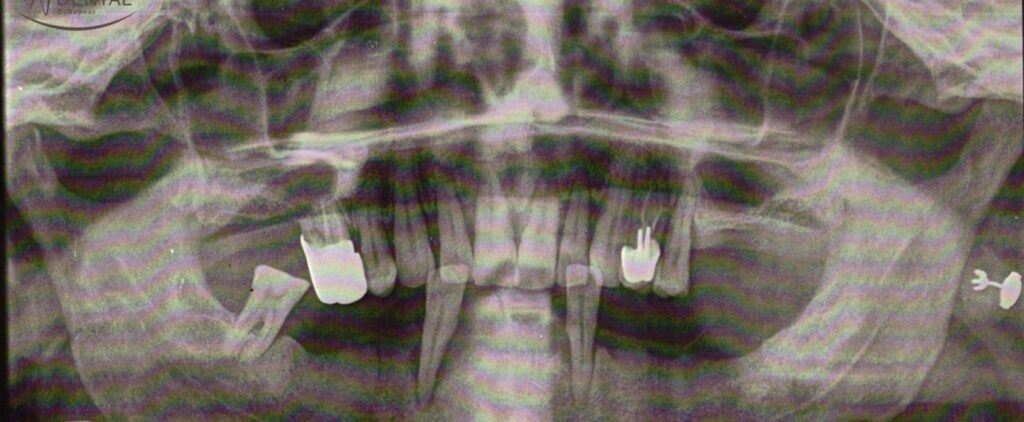

Notre patient qui est un gros fumeur a développé une maladie parodontale sévère. Toutes ses dents ont dû être extraites

Notre patient gros fumeur (qui a évité les examens dentaires et les détartrages pendant des années) a développé une maladie parodontale sévère qui a attaqué non seulement ses propres dents mais aussi les implants posés (inflammation autour de l'implant - périimplantite).